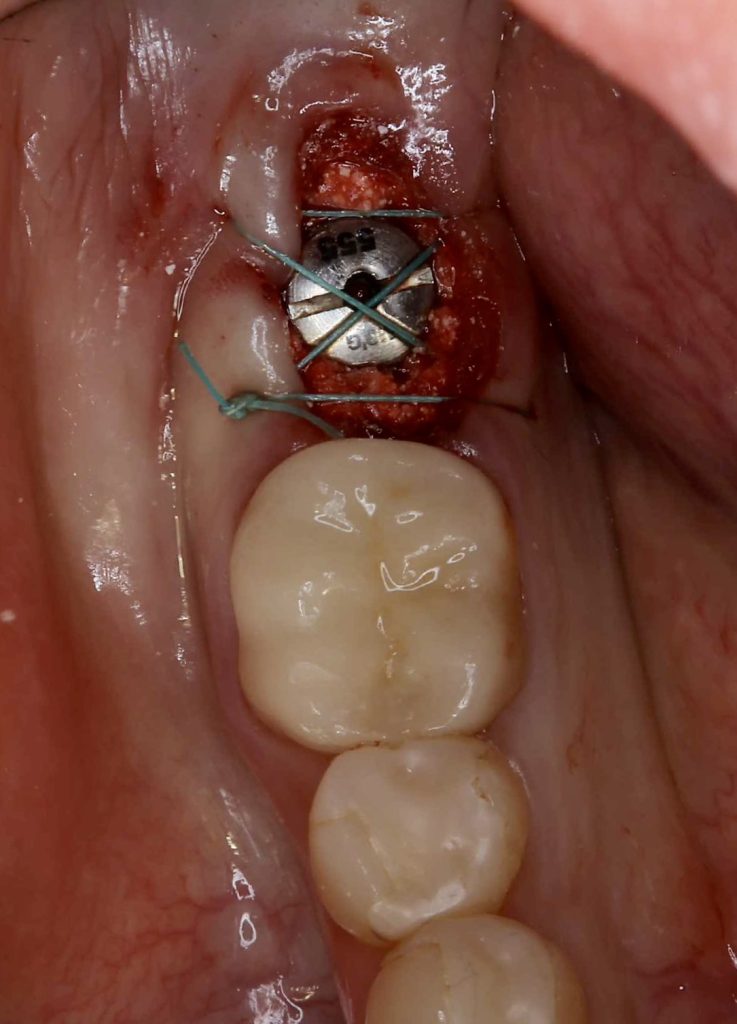

30代、女性、右下に違和感があることを健診中に申され、インプラント治療を行いました。

| 診断結果 | 右下7番歯根破折 |

| 治療内容 | 抜歯即時インプラント |